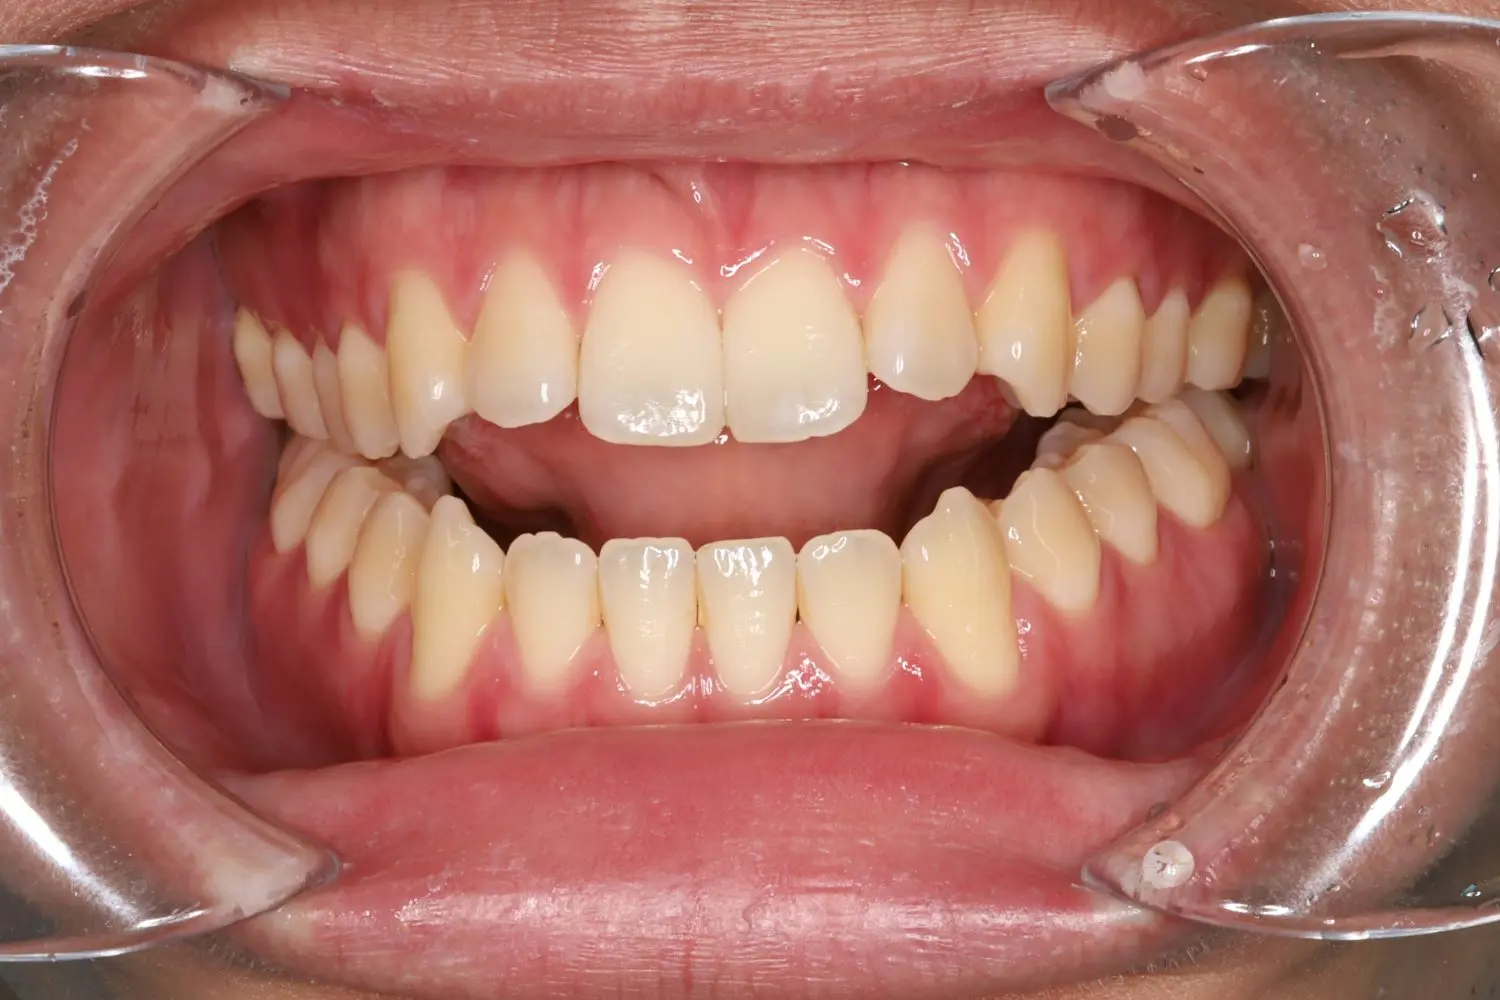

| 年齢 | 50代女性 |

| 主訴 | ガタガタ |

| 治療期間・治療回数 | 2年3か月 |

ガタガタの程度が強いため、4本抜歯することで叢生を改善するスペースを確保しました。年齢とともに歯が動きづらくなりますが、矯正治療は十分に行えます。無理のない治療計画で歯肉退縮など副作用を抑えられました。